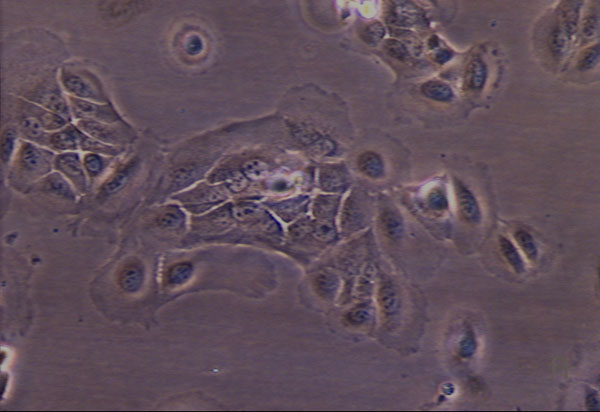

Figure 3 a:

Phase contrast,